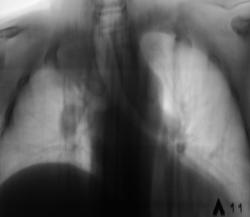

Два года тому поциентке произведена мастэктомия по поводу рака молочной железы. Направлена врачом онкологом (из области) для рентгенографии органов грудной полости. Произведено исследование.

Картина новообразования справа на верхушке, периферического, отсутствие переднего фрагмента 4 ребра справа, релаксация или приподнятость правого купола диафрагмы. Если при рентгеноскопии наличствует парадоксальная подвижность диафрагмы - парез диафрагмального нерва - мета в средостение, если нет - УЗИ печени - искать причину приподнятости купола там.

Как Вам второй вариант: после мастэктомии часто проводят лучевую терапию на над-подключичные л/узлы на стороне опухоли (в данном случае справа), естественно в поле облучения попадает в/доля легкого, где развивается сначала пневмонит, затем фиброз, возможен цирроз. Эти изменения очень вариабельны и зависят от индивидуальной чувствительности. На снимке, кстати, правый корень подтянут вверх, трахея подтянута вправо, в/доля уменьшена в объеме и неравномерно уплотнена. С чего бы этому быть при периферическом образовании? Касательно переднего отрезка 4 ребра справа - он действительно четко не прослеживается, но прозрачность легочного фона в этой зоне повышена, думаю, что снимок на этом участке "перебит" из-за того, что нет молочной железы. Рекомендую уточнить анамнез на предмет лучевой терапии, поднять снимки из архива, если нет такой возможности или остаются сомнения - направить на КТ. На передний отрезок 4 ребра справа требуется сделать прицеленый снимок.

Насчет ребра: патология там - безусловно есть, оно выпадает из реберного ряда уже на уровне приблизительно средней подмышечной линии...

На мой взгляд, скорее всего здесь имеет место постлучевой фиброз в верхней доле справа с уменьшением объема части легкого. Но для исключения новообразования я бы порекомендовал пройти КТ. Рисковать не стоит.

Затенение в S1, не похоже на перферический рак т.к. последнее всё таки узловое образование.Трахея перетянута вправо- скорее это постлучевой фиброз ( хотя картина несколько необычная, т.к. как правило,при лучевом фиброзе тени тяжистого характера).Нужно КТ( в4 ребре патология).